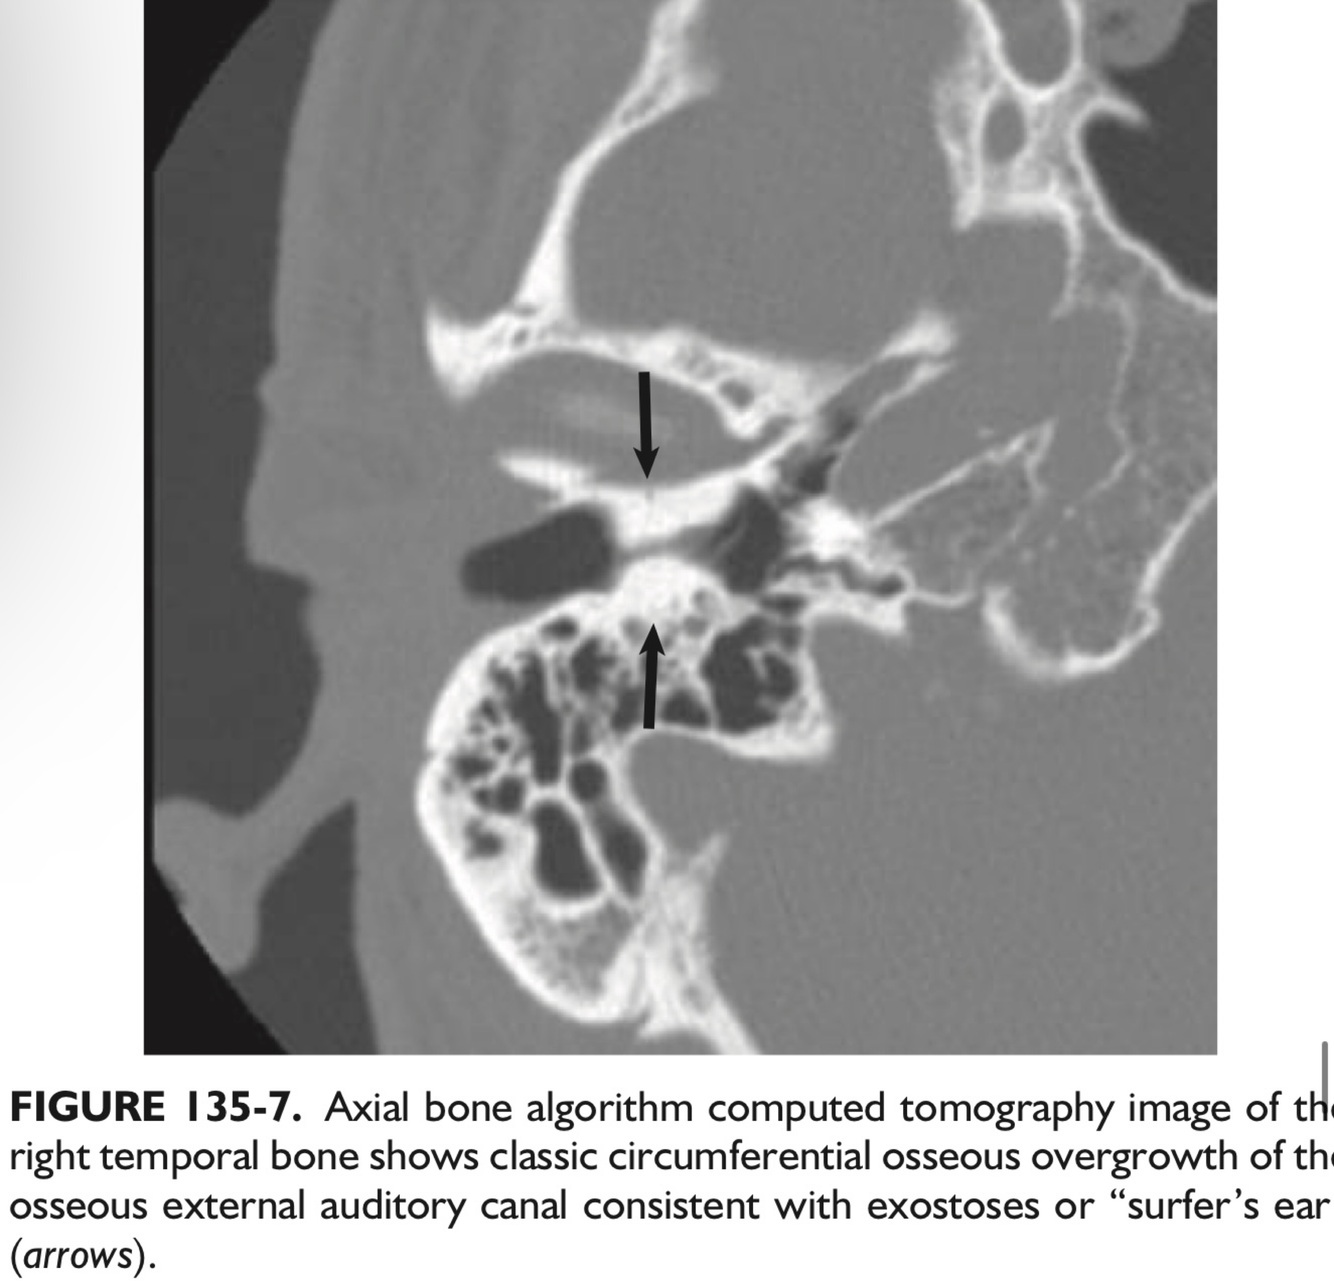

_____, a benign neoplasm of the EAC, are known as “surfer’s ear” frequently seen on imaging in some regions where cold water swimming is common.

They are almost always ___ and typically occur at the ___.

Exostoses.

Bilateral, and typically occur at the suture lines.